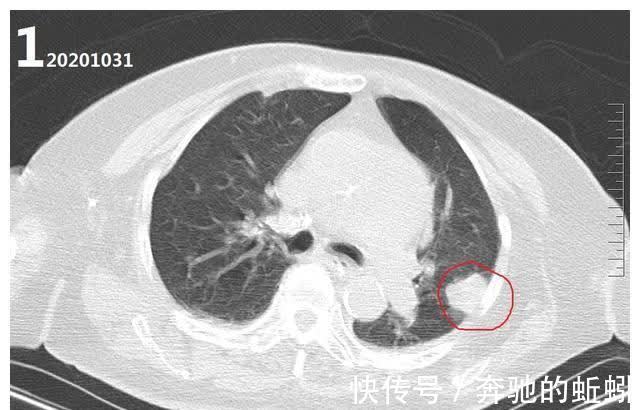

术后两天也就是10月31号复查CT发现左肺有一个肿块,性质不明确(图1),考虑肿瘤。因该患者正处在动脉瘤血管内栓塞手术术后恢复期,主要矛盾仍为动脉瘤性蛛网膜下腔出血及其并发症所致,故未对肺部病变进行进一步诊治。